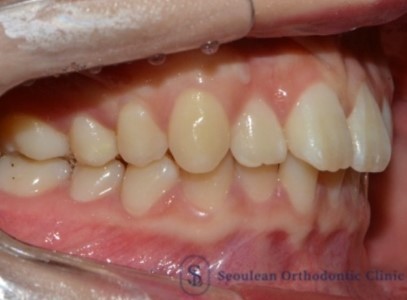

상·하악 중심선 비대칭과 2급·3급 구치관계, 비발치 교정으로 1급 교합 회복한 20대 여성 사례